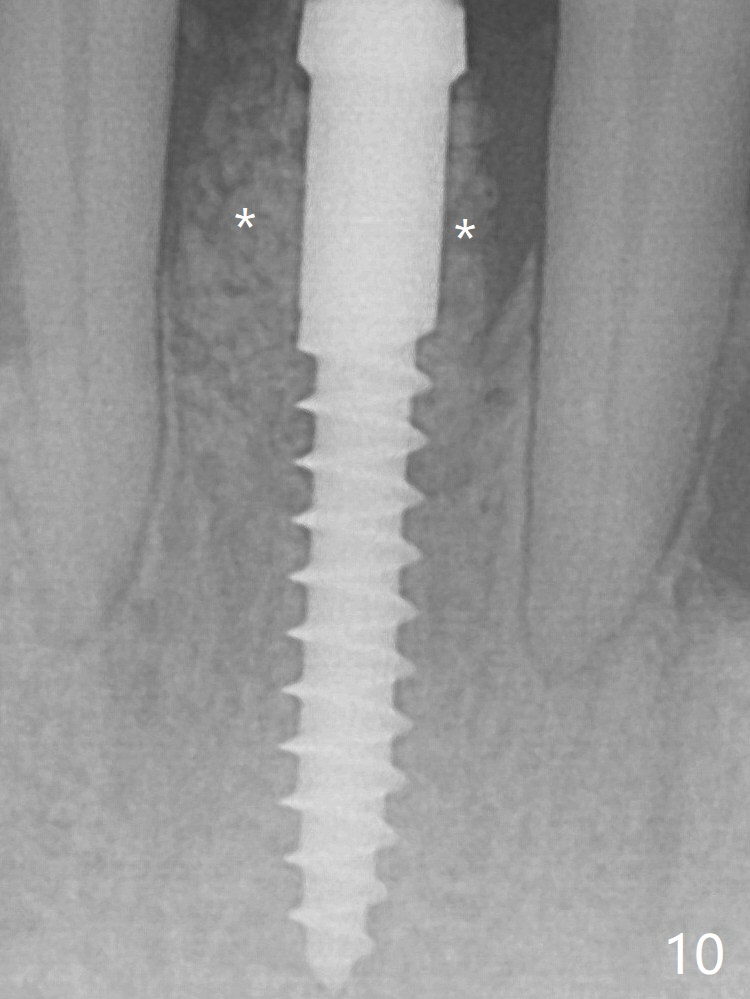

Because of the narrow flat ridge buccolingually, a 2.5x12(4) mm 1-piece implant is placed with >40 Ncm (Fig.8). With deeper placement of the implant, Vanilla graft is placed in 2 steps (Fig.9,10 *). No implant threads are exposed 10 months postop (Fig.11).